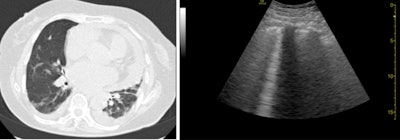

Notably, Chen also used ultrasound to identify left ventricular dysfunction and pericardial effusion in one patient with COVID-19 who didn't have any abnormal lung findings on ultrasound or chest CT. This highlighted the usefulness of ultrasound to identify other types of COVID-19 complications, a benefit that has been documented in other studies.

The main drawback of lung ultrasound is that the modality can lead to disease misclassification, as it did for three patients in this study who were ultimately diagnosed with viral bronchitis and pulmonary metastatic disease based on CT findings. Nevertheless, the authors felt confident recommending ultrasound as an imaging tool for COVID-19 based on its excellent sensitivity, ease of infection control, and portability.